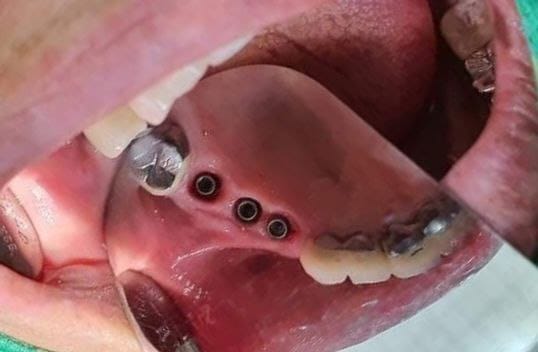

يتم إجراء عمليات الزرع في مراكزنا من قبل فريق من أخصائي زراعة الأسنان ذوي المهارات العالية وأطباء الأسنان التجميليين للحصول على دقة جراحية متميزة وجماليات ممتازة للابتسامة

يترأس مراكزنا فريق مختار بعناية من خبراء زراعة الأسنان. وبعد عملية الزرع يتم تركيب التيجان والجسور ، والتي يتم تصميمها بأقصى قدر من الدقة والجمالية لمنحك الابتسامة المثالية.